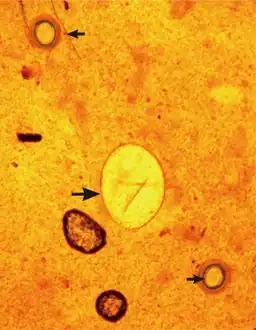

The eggs (ova) of Echinostoma are operculate [4] and vary in size, but are typically in the range of 80-135μm × 55-80μm.[7]

An Echinostoma ilocanum egg (larger arrow)

An Echinostoma infection can be diagnosed by observing the parasite eggs in the faeces of an infected individual, under a microscope. Methods such as the Kato-Katz procedure can be used to do this.[3] The eggs typically have a yellow-brown appearance, and are ellipsoid in shape.[20] To confirm which species is causing the infection adult worms must be recovered from the infected individual, such as with anthelmintic treatment.[20]